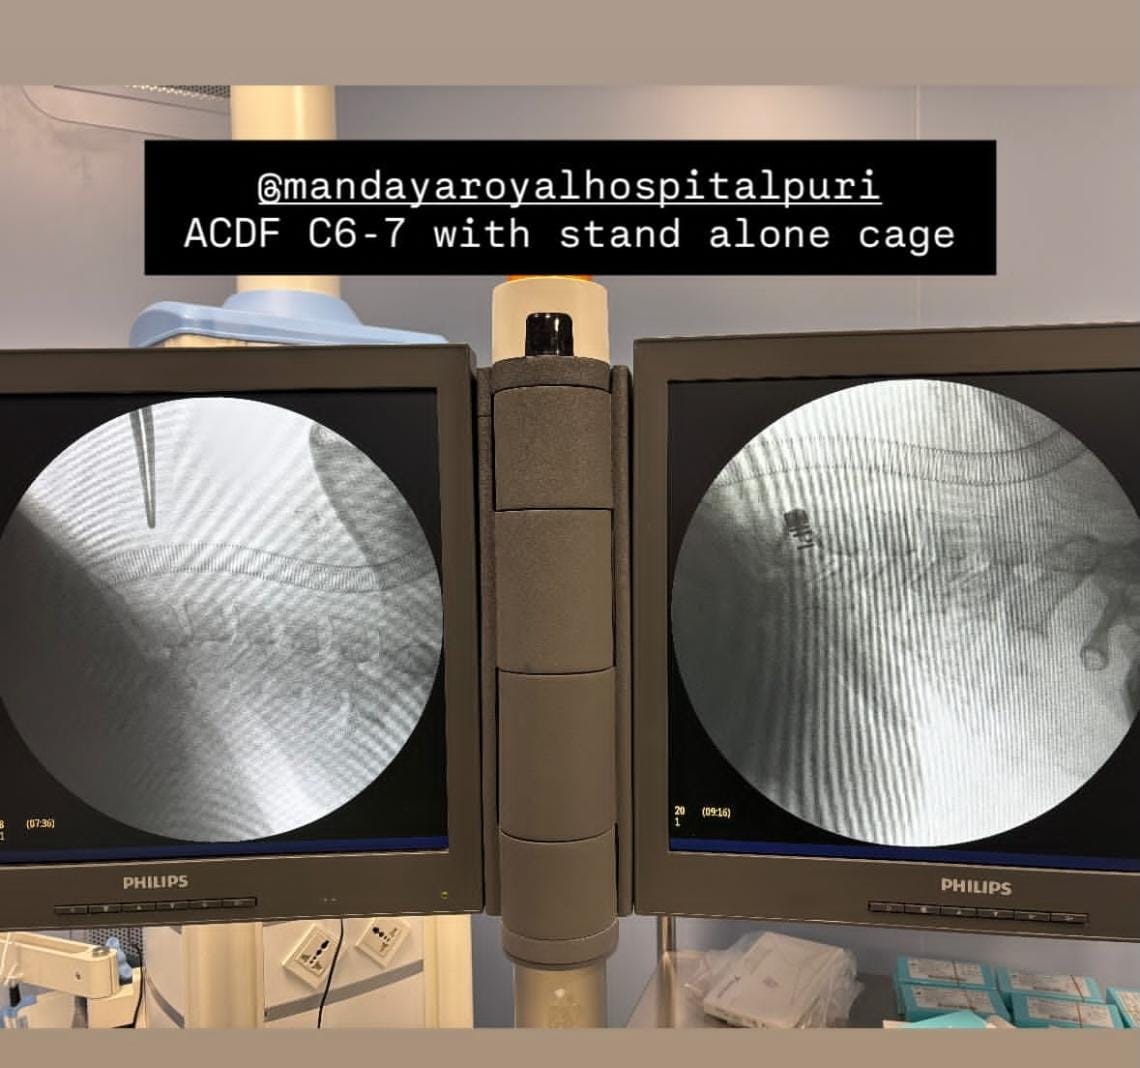

Anterior Cervical Discectomy and Fusion (ACDF)

Anterior Cervical Discectomy and Fusion (ACDF) adalah jenis operasi leher yang melibatkan pengangkatan diskus yang rusak untuk meringankan tekanan tulang belakang atau tekanan akar saraf dan mengurangi rasa sakit, kelemahan, mati rasa, dan kesemutan.

– Pasien ACDF level C6-C7 –